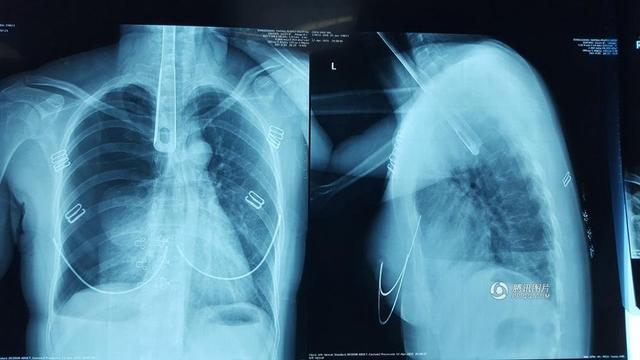

广东省东莞市虎门镇一30多岁的陈女士在家炒菜,突然觉得喉咙堵得难受,好像里面有个很大的“疱”。她先是用手指往喉咙里抠,

抠不着,又用筷子去捅,筷子还是不够长。她于是拿起炒菜用的30多厘米长的铝合金锅铲,用锅铲把手往喉咙里捅了进去……